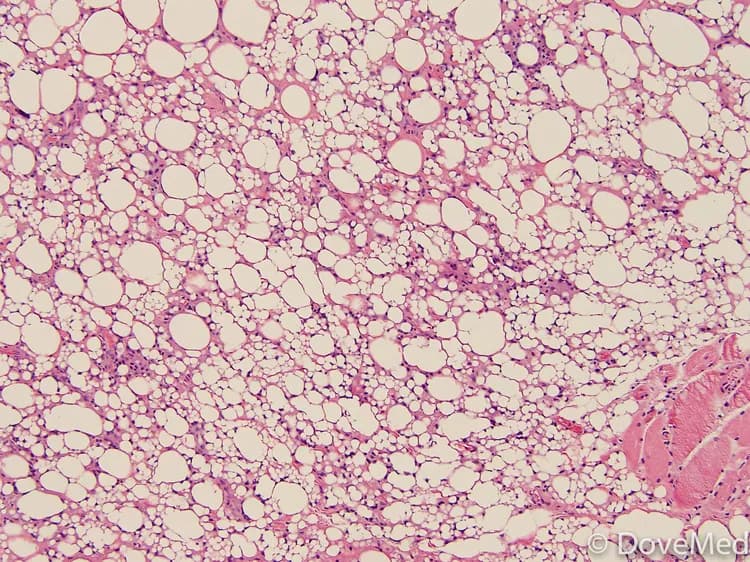

• Lipoma of Pancreas is a benign tumor of the pancreas consisting of fat tissues (adipose tissues). It typically occurs in middle-aged and older adults

• Tissue biopsy: A tissue biopsy is performed and sent to a laboratory for a pathological examination to the pathologist, who examines the biopsy under a microscope. After putting together clinical findings, special studies on tissues (if needed) and with microscope findings, the pathologist arrives at a definitive diagnosis